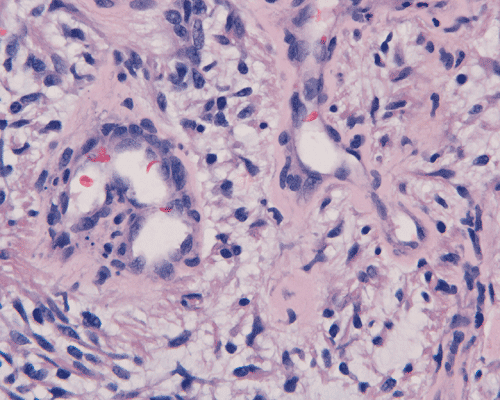

In a substantial amount of area, the tumor is composed of spindle cells with prominent perivascular arrangment and microcyst formation (Panel A and B). These vessels are surrounded by a thin rim of bipolar spindle cells (Panel C). The paucicellular perivascular mantle that is typical for ependymoma is absent in these perivascular arrangements. Adjacent to these perivascular arrangment is substantial amount of myxoid changes. On high-magnification, the tumor cells appear bland in histology, bioplar and spindle in shape, and admixed with a large amount of myxoid substance (Panel D and E). There is a lack of mitosis or significant pleomorphism. In some areas, the tumor is composed exclusively of spindle cells in a myxoid background with microcyst formation but without perivascular coronary arrangement of tumor cells (Panel F). It is not uncommon to observe areas with spindle cells clinging to the blood vessels (Panel G). In a minority of areas, there is increase in cellularity (Panel H). Some vessels seem to be composed of glomeruloids of blood vessels with plump endothelial cells (Panel I).

Histologically, the salient features of PMA are rather monotonous, small, spindle bipolar cells with angiocentric arrangement within a strikingly myxoid background. The myxoid basckground material is positive for Alcian blue but negative for PAS 1, 3,.  These features are well illustrated in our case. Occasional necrotic foci and mitotic figures can be present. Atypical mitotic figures and substantial nuclear pleomorphism should not be seen. Occasionally, the tumor cells infiltrate the surrounding non-neoplastic brain parenchyma but neither the histological feature nor radiological features would suggest a diffusely infiltrating astrocytoma. In contrast to pilocytic astrocytomas, PMAs do not possess a true alternating densely packed-loosely packed biphasic pattern, do not contain eosinophilic granular bodies or Rosenthal fibers 1, 4. Development of features that are seen in pilocytic astrocytomas such as the biphasic pattern and Rosenthal fibers have been described by Fernandez et al 4. These features are uncommon at the initial presentation but they can develop after chemotherapy. Although these features may suggest maturation of the tumor after chemotherapy, no association with improved prognosis has been described in the study by Fernandez et al 4. The angiocentric arrangement of tumor cells is another trap as it would suggest ependymoma. However, these arrangements are more irregular and fibrillar than the perivascular rosettes in ependymomas.